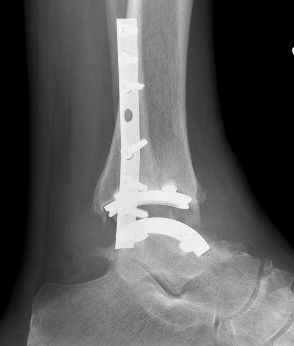

Infinity implant STAR implant Inbone

Agility Salto Tolaris Trabecular metal